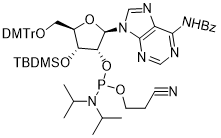

馬鞍山致研生物醫(yī)藥科技有限公司成立于馬鞍山市鄭浦港新區(qū)現(xiàn)代產(chǎn)業(yè)園。公司專(zhuān)注于生物小分子、醫(yī)藥中間體相關(guān)產(chǎn)品的研發(fā)和生產(chǎn),產(chǎn)品主要包括DNA亞磷酰胺單體、RNA亞磷酰胺單體、特殊單體以及按照客戶(hù)要求定制的RNA和DNA,并且公司提供定制合成等方面的研究服...

馬鞍山致研生物醫(yī)藥科技有限公司成立于馬鞍山市鄭浦港新區(qū)現(xiàn)代產(chǎn)業(yè)園。公司專(zhuān)注于生物小分子、醫(yī)藥中間體相關(guān)產(chǎn)品的研發(fā)和生產(chǎn),產(chǎn)品主要包括DNA亞磷酰胺單體、RNA亞磷酰胺單體、特殊單體以及按照客戶(hù)要求定制的RNA和DNA,并且公司提供定制合成等方面的研究服...